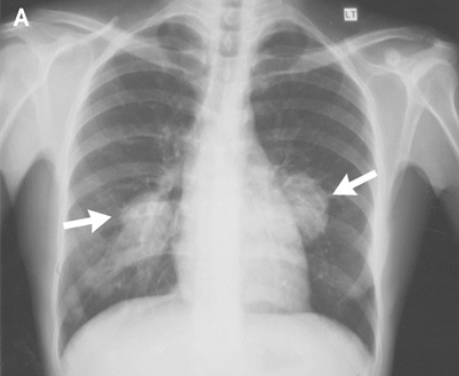

sacral Fx with bone marrow edema, avoid exercise